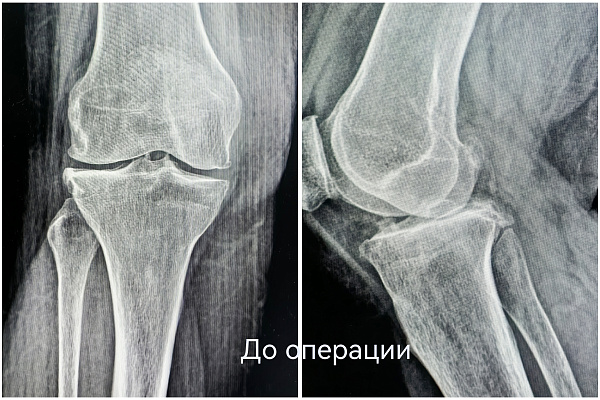

Чтобы избавиться от мучительной боли в колене, наша 55-летняя пациентка готова была избавиться от всего сустава. При госпитализации женщина настроилась на эндопротезирование. Однако травматологи-ортопеды выбрали другую тактику. При вальгусной деформации и деформирующем артрозе второй стадии коленный сустав оставался достаточно сохранным. Чтобы спасти его от замещения металлоконструкцией, была выполнена корригирующая остеотомия.

Суть операции – в исправлении нарушенной оси конечности. После перестроения и выравнивания костей голени нагрузка собственного веса смещается с пораженной части сустава на здоровую. Таким образом, болевой синдром регрессирует, а износ сустава замедляется.

В случае с этой пациенткой ради сохранения коленного сустава пришлось пожертвовать 10 миллиметрами большеберцовой кости. Костный клин такого размера был удалён, чтобы вернуть конечность в правильную механическую ось. Небольшие размеры современных фиксаторов позволяют выполнять операции малотравматичным доступом – через 4-5-сантиметровый разрез.